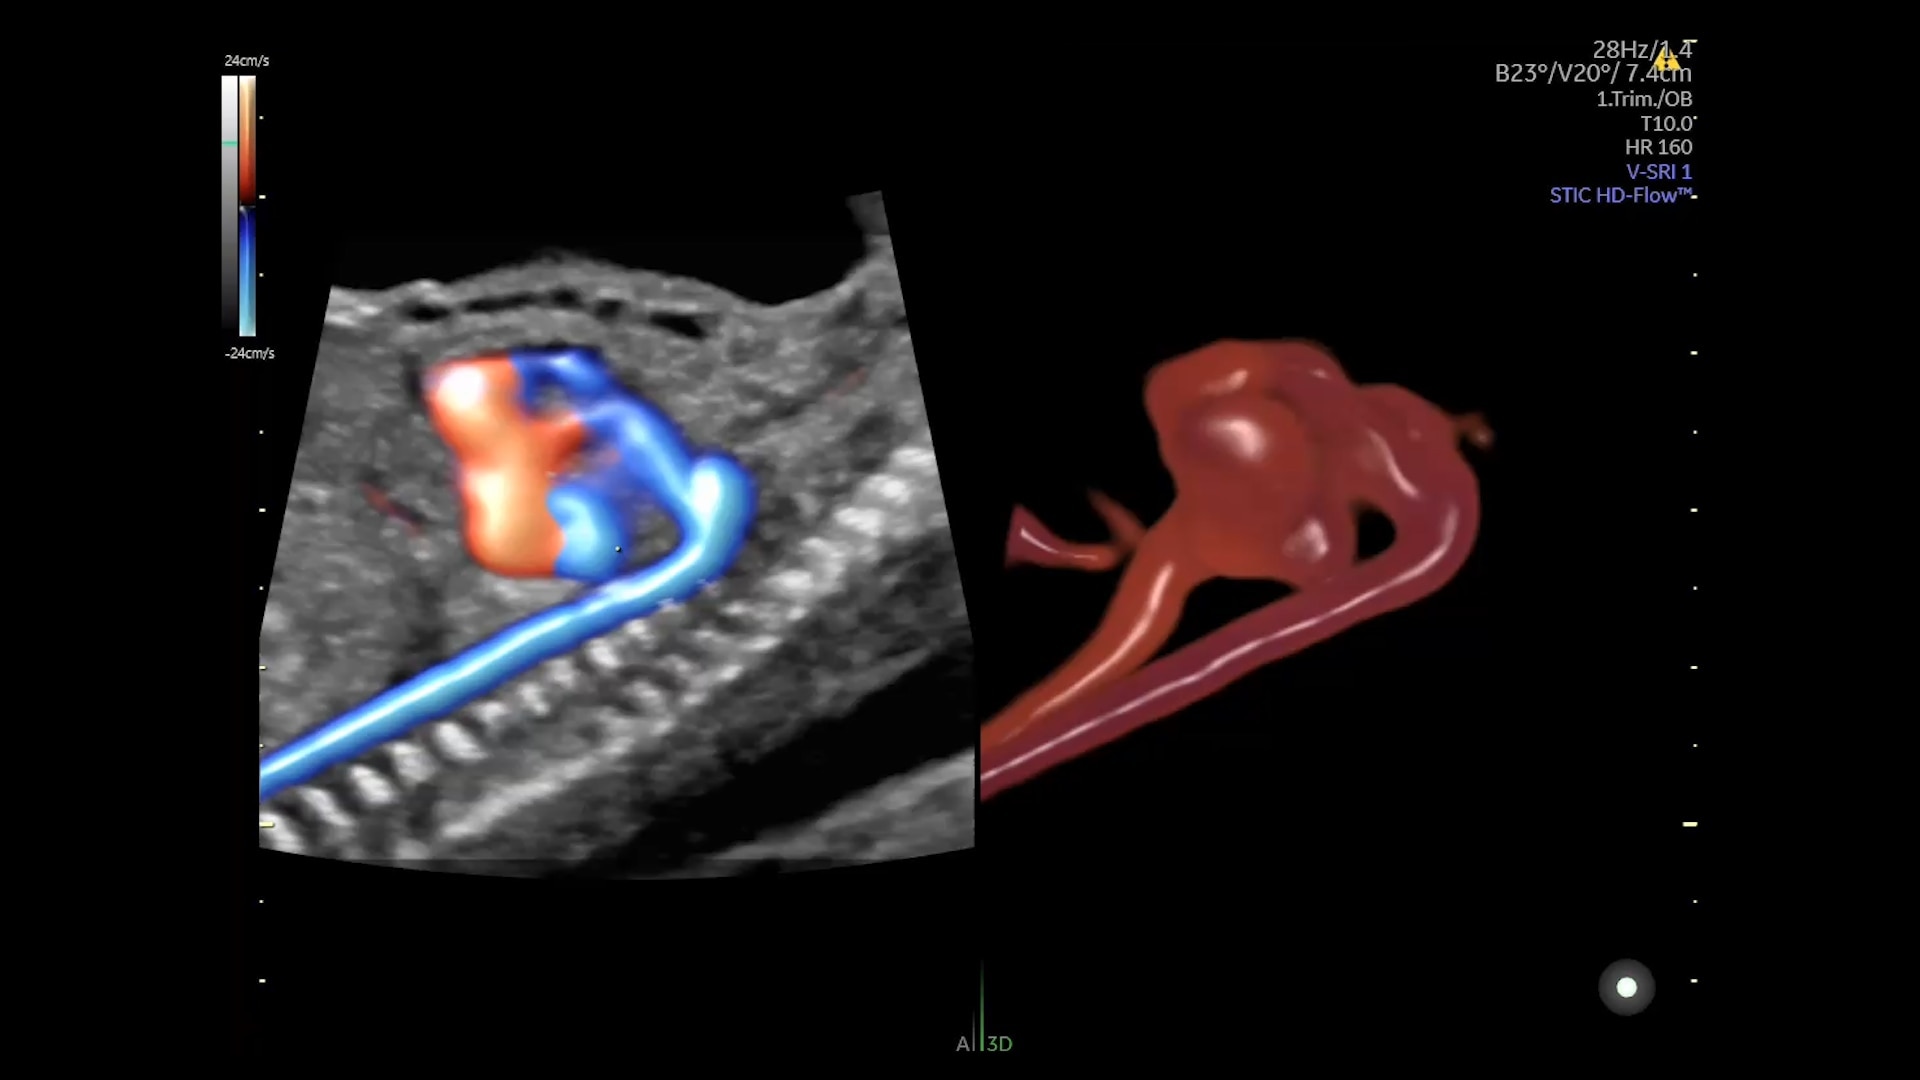

Graphicflow

Hemodynamic Visualization

Provides a graphical representation of the trajectories of the blood cells in real-time to visualize complex blood flow quickly and clearly, helping you to differentiate normal from abnormal hemodynamics